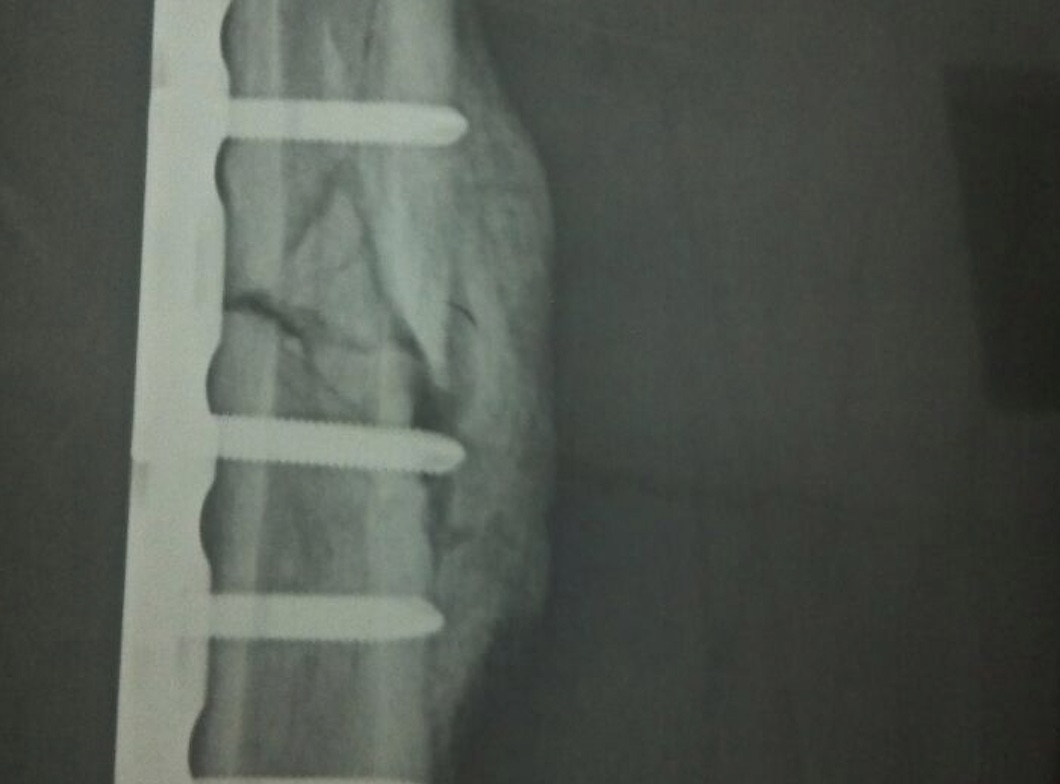

骨折后2-3天,肉眼观及X线检查可见骨折局部呈梭形肿胀,X线片可见局部有低于骨质的高密度影,为骨痂,骨折恢复过程中骨痂密度逐渐增高,最终接近正常骨质密度。出现骨痂说明骨折在逐渐恢复,可能伴随疼痛、肿胀、瘀斑、畸形、功能障碍,以及骨擦音和骨擦感等症状。